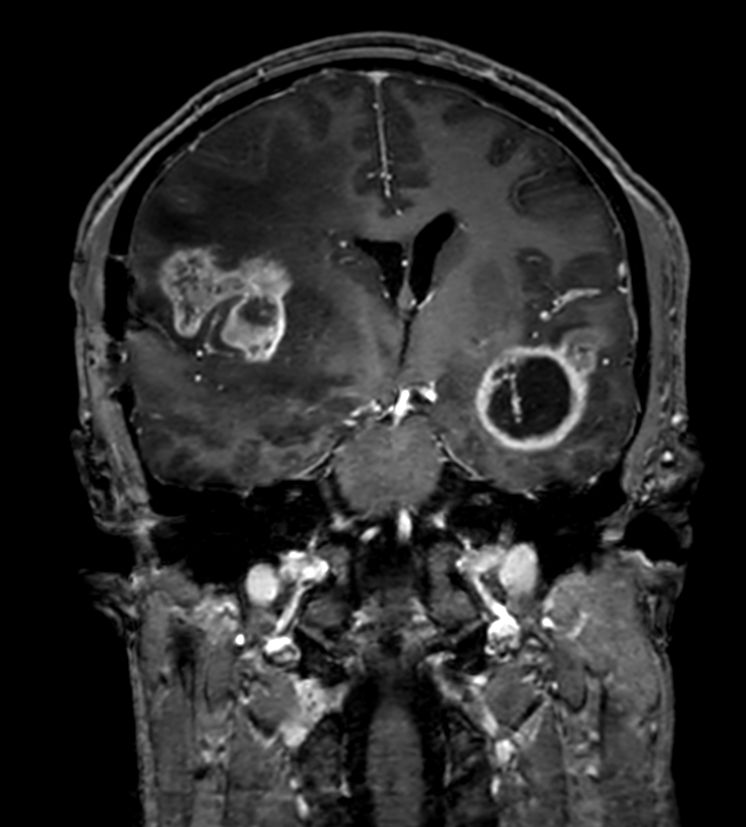

3D T1w TFE (Coronal reformat)Post-Gado